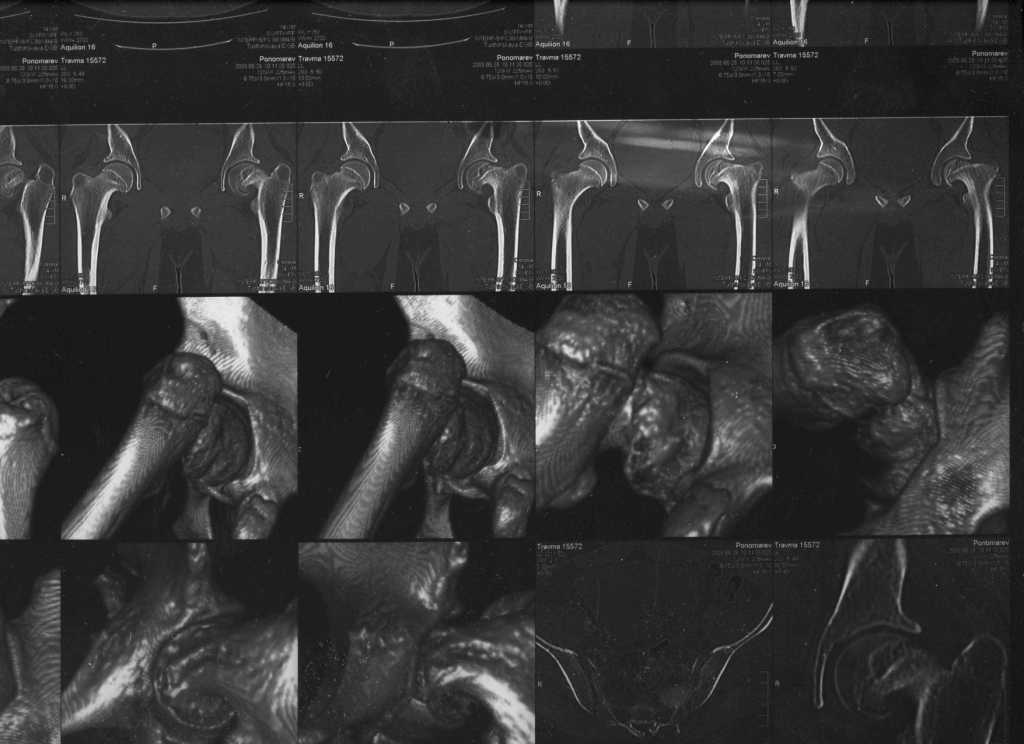

Ребёнок 14 лет. Весом под центнер. Имеющаяся рентгенологическая деформация деформация - на момент поступления. Госпитализирован ребёнок 14 лет. Мальчик, мягко говоря, крупный, гиперстенического типа сложения, ближе к десантнику. Весит 95 кг. Ожирение 2-й степени. Со слов больного - испытывает дискомфорт в области тазобедренного сустава в течение 3-х месяцев. На рентгенограммах - положение дел на момент поступления - конец мая. Укорочение конечности на 1,5 см. Ограничение внутренней ротации. Ходит, едва заметно прихрамывая на больную ногу. Эндокринологический статус находится в стадии обследования. Выполнена рентгенография в стандартных укладках, спиральная КТГ.Ясное дело, головка бедра <ушла> вниз и кзади. Пытающаяся <поймать> её шейка варизировалась и исполнила ретроверсию, создав изгиб во фронтальной плоскости. На рентгеноскопии - подвижность головки не определяется. Мальчик имеет далеко идущие планы на обустройство собственной жизни и образование. Крайне негативно относится к длительной иммобилизации и консервативному лечению. Загодя не согласен со снижением качества жизни в процессе лечения. Мнения коллег относительно дальнейшего лечения разделились. Успешность репозиции головки под наркозом - сомнительная в связи с имеющейся деформацией шейки бедра. Одни склоняются к тактике невмешательства - разгрузка больной конечности, ФЗТ , массаж, и т.д. Предлагают ждать завершения процесса <сползания> головки в условиях полной разгрузки, <тянуть> сустав до эндопротезирования как можно дольше. Другая группа коллег предлагает немедленную стабилизацию головки, что, кажется, правильно. Принимая во внимание анатомическое соотношение головки и шейки бедра, способ остеосинтеза так же вызвал массу споров, не приведших к единому и окончательному мнению. Пока дискуссия остановилась на стабилизации спицами Бека под контролем ЭОП, возможно с применением электродов для проведения электростимуляции слабыми импульсными токами. Техника проведения спиц, однозначно, будет сопряжена с техническими трудностями, обусловленными имеющейся деформацией шейки. Как бы Вы поступили, коллеги, в данной ситуации?Заранее спасибо. И прошу прощения за качество спимков. Буду отправлять их по очереди.

Здравствуйте Данил. По представленным рентгенограммамам и кт срезам Вы имеете дело хронической, стабильной формой ЮЭГБК. Шеечно- эпифизарная деформация выраженная, эпифиз отклонён кзади более чем на 70 градусов, практически до упора в межвертельную ямку, что характеризует её как тяжёлую степень. В выборе метода лечения мы придерживаемся следующей схемы: